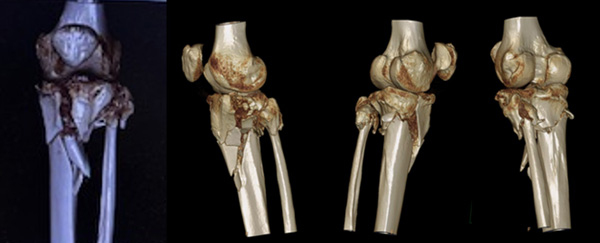

Final strategy decision

• Hardware Removal

• Tibial plateau leveling osteotomy

• Elevation of the inverted dome (only) medially

• Fixation with 2 plates

• The objective was to preserve the native articulation and cartilage, (which is not so bad), correct the slope and the varus in the same procedure to treat the flexum and achieve proper alignment for a possible future simple TKA.

Post-operative X-Rays

1 month

• Complete extension

• Flexion 140

• Symetric varus